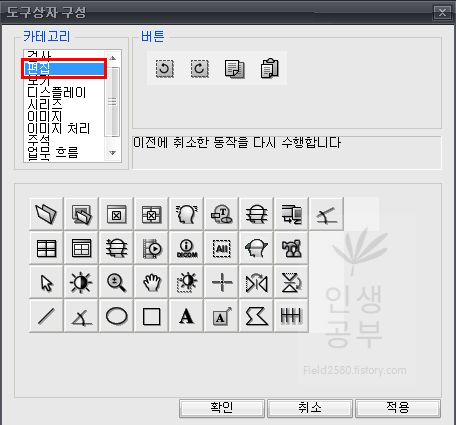

위와 같은 도구상자 구성 화면이 뜨게 됩니다. 아래에는 현재 사용중인 도구상자들이고 왼쪽 상단에는 도구상자에 넣을 수 있는 카테고리들이 있습니다. 카테고리칸 옆에는 버튼칸이 있고 아래 도구상자칸에 없는 메뉴들도 많이 있습니다. 아이콘에 마우스를 가져다 대면 간단한 설명이 나오니 필요하신 분들은 한번씩 다 확인해보시는 걸 추천해드립니다.

그 후에 저는 마지막으로 한 동작을 취소합니다 버튼과 이전에 취소한 동작을 다시 수행합니다 버튼을 많이 사용하기 때문에 추가했습니다. 카테고리에 있는 편집을 클릭해 주세요.

제일 앞에 있는 버튼이 마지막으로 한 동작을 취소합니다 버튼입니다. 버튼을 드래그해서 아래로 끌어다 줍니다.